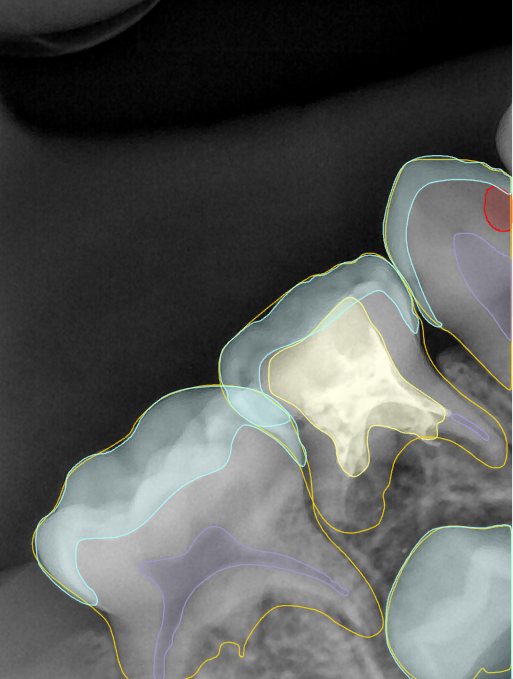

CR/DR 牙齿分割阶段记录

当前进展

- 完成了 CR/DR 牙齿相关分割训练

- 当前结果已经达到阶段预期,但仍有细节问题需要继续处理

相关测试

遇到的问题

- 训练过程中出现过 mask 下移问题

- 部分结果会出现 box 填充异常

- mask 边缘仍然有比较明显的锯齿感

参考

第二版算法问题测试